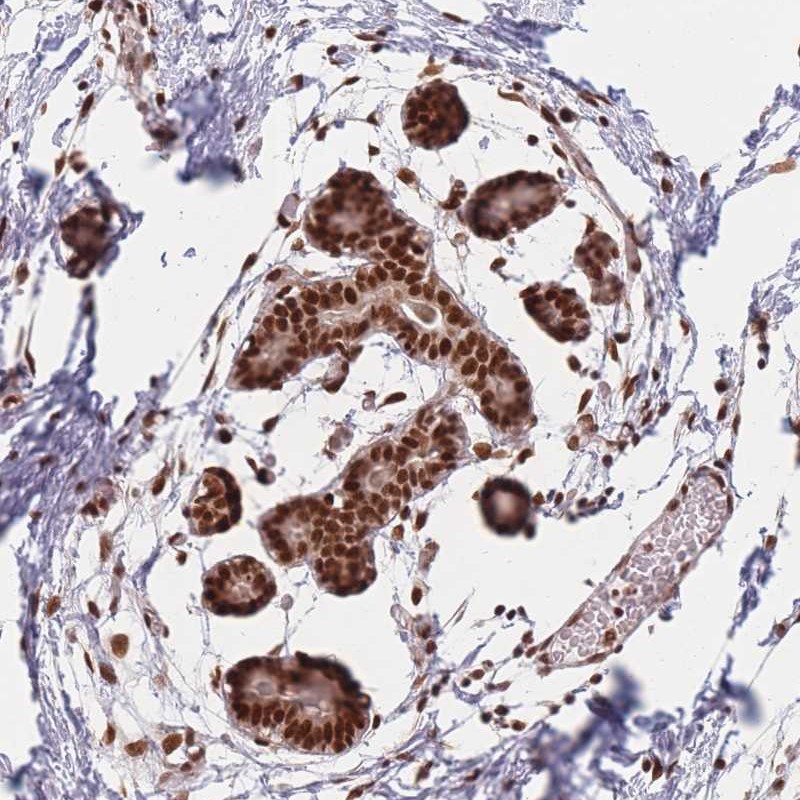

Immunohistochemical staining of human breast shows strong nuclear positivity in glandular cells and myoepithelial cells.